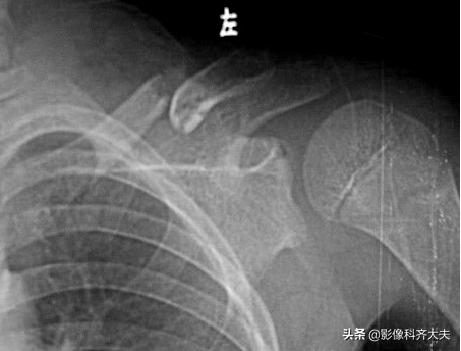

锁骨两断端骨髓腔闭合,明显错位,形成假关节。

骨折畸形愈:

骨折断端对合不良,可造成肢体缩短和成角畸形等

右锁骨骨折后畸形愈合,对线不良,右锁骨明显变短